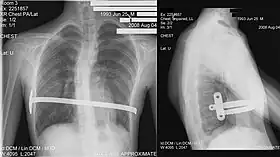

His two-stage procedure, widely known as the Nuss procedure, involves slipping in one or more concave steel bars into the chest, underneath the sternum.[56]

The bar is flipped to a convex position so as to push outward on the sternum, correcting the deformity. The bar usually stays in the body for about two years, although many surgeons are currently moving toward leaving them in for up to five years. When the bones have solidified into place, the bar is removed through outpatient surgery.

The Ravitch technique is an invasive surgery that was introduced in 1949[51] and developed in the 1950s. It involves creating an incision along the chest through which the cartilage is removed and the sternum detached. A small bar is inserted underneath the sternum to hold it up in the desired position. The bar is left implanted until the cartilage grows back, typically about six months. The bar is subsequently removed in a simple outpatient procedure; this technique is thus a two-stage procedure.